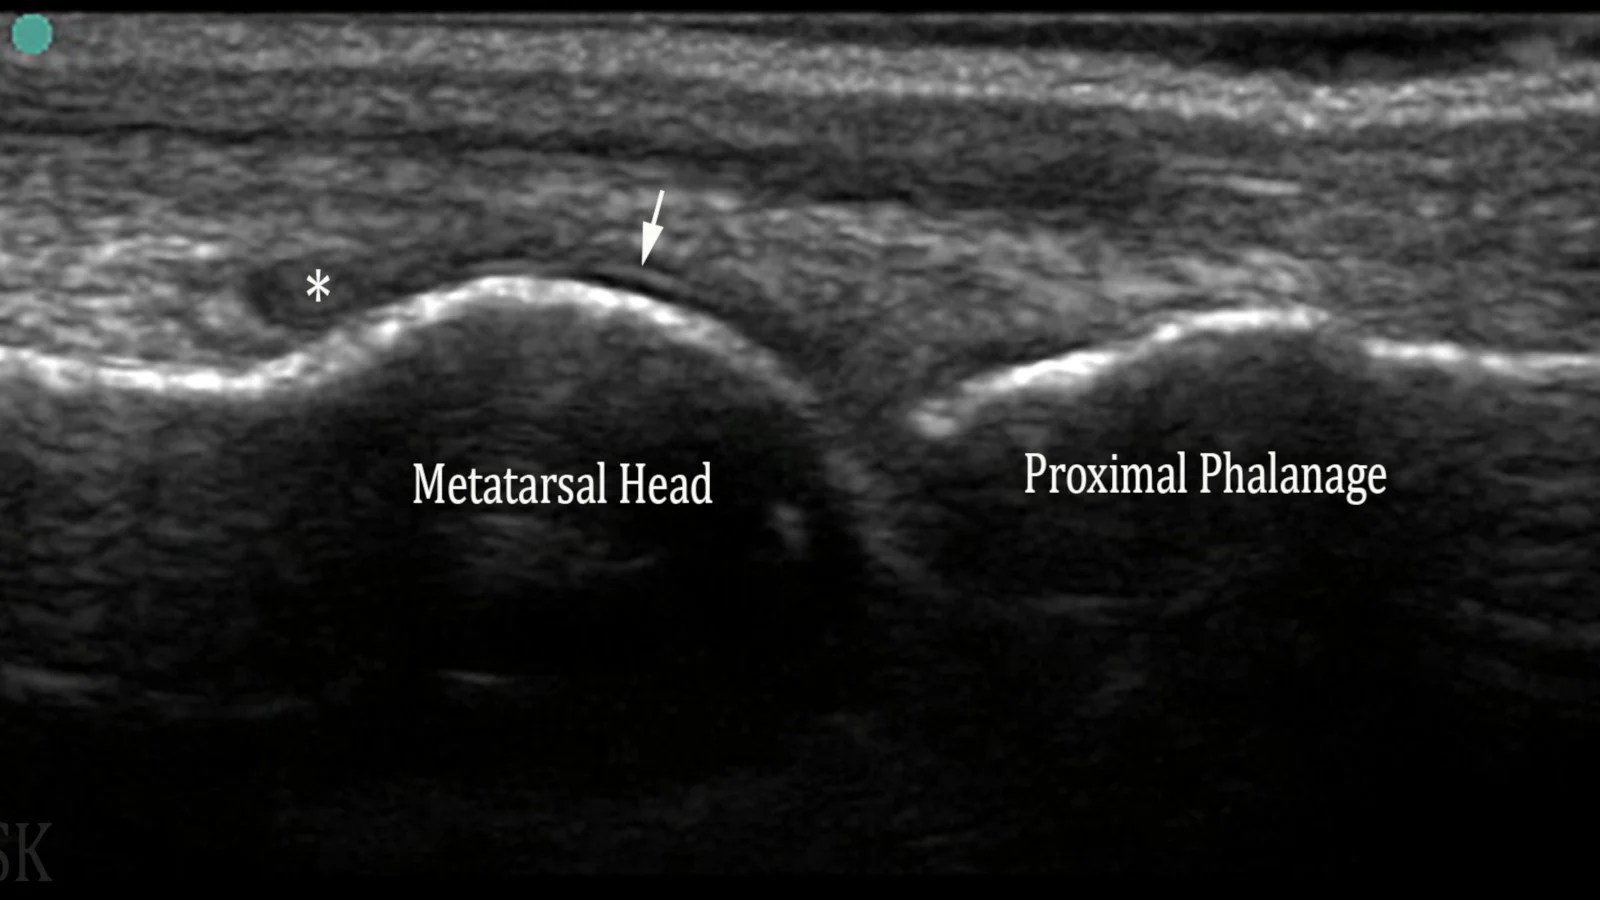

From mskultrasound.net

Gout Book Of MSK Ultrasound Is Ultrasound Therapy Good For Gout New guidelines and recommendations have addressed the diagnosis and treatment of gout. The use of ultrasonography (us) has considerable potential for the diagnosis and monitoring of gout due to its capacity to detect. An undelayed diagnosis and an early therapeutic intervention using uric acid lowering therapy (ult) is of the utmost importance for preventing bone. Ultrasound is a clinically convenient. Is Ultrasound Therapy Good For Gout.

From theultrasoundsite.co.uk

mskultrasound photo Is Ultrasound Therapy Good For Gout Imaging has been shown to be able to detect a wide range of abnormalities in gout, and therefore may be applied to its diagnosis, clinical monitoring, and management. An undelayed diagnosis and an early therapeutic intervention using uric acid lowering therapy (ult) is of the utmost importance for preventing bone. The use of ultrasonography (us) has considerable potential for the. Is Ultrasound Therapy Good For Gout.

Gout Book Of MSK Ultrasound Is Ultrasound Therapy Good For Gout Imaging has been shown to be able to detect a wide range of abnormalities in gout, and therefore may be applied to its diagnosis, clinical monitoring, and management. New guidelines and recommendations have addressed the diagnosis and treatment of gout. Ultrasound is a clinically convenient approach to detect msu crystal deposits in. The use of ultrasonography (us) has considerable potential. Is Ultrasound Therapy Good For Gout.